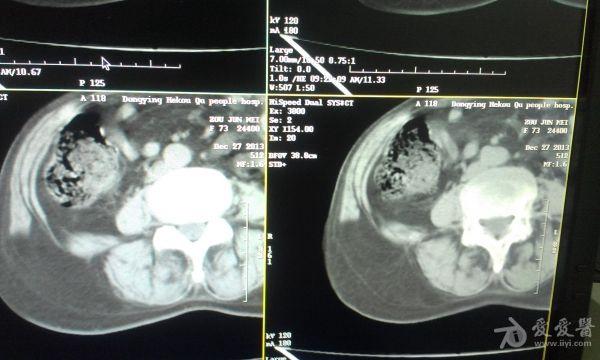

挺经典的腰疝

右腰部包块,随呼吸可运动。

非常经典的ct片,不知是继发于何种原因还是先天性的?里面内容物一般是肠管,很少发生较窄、嵌顿。